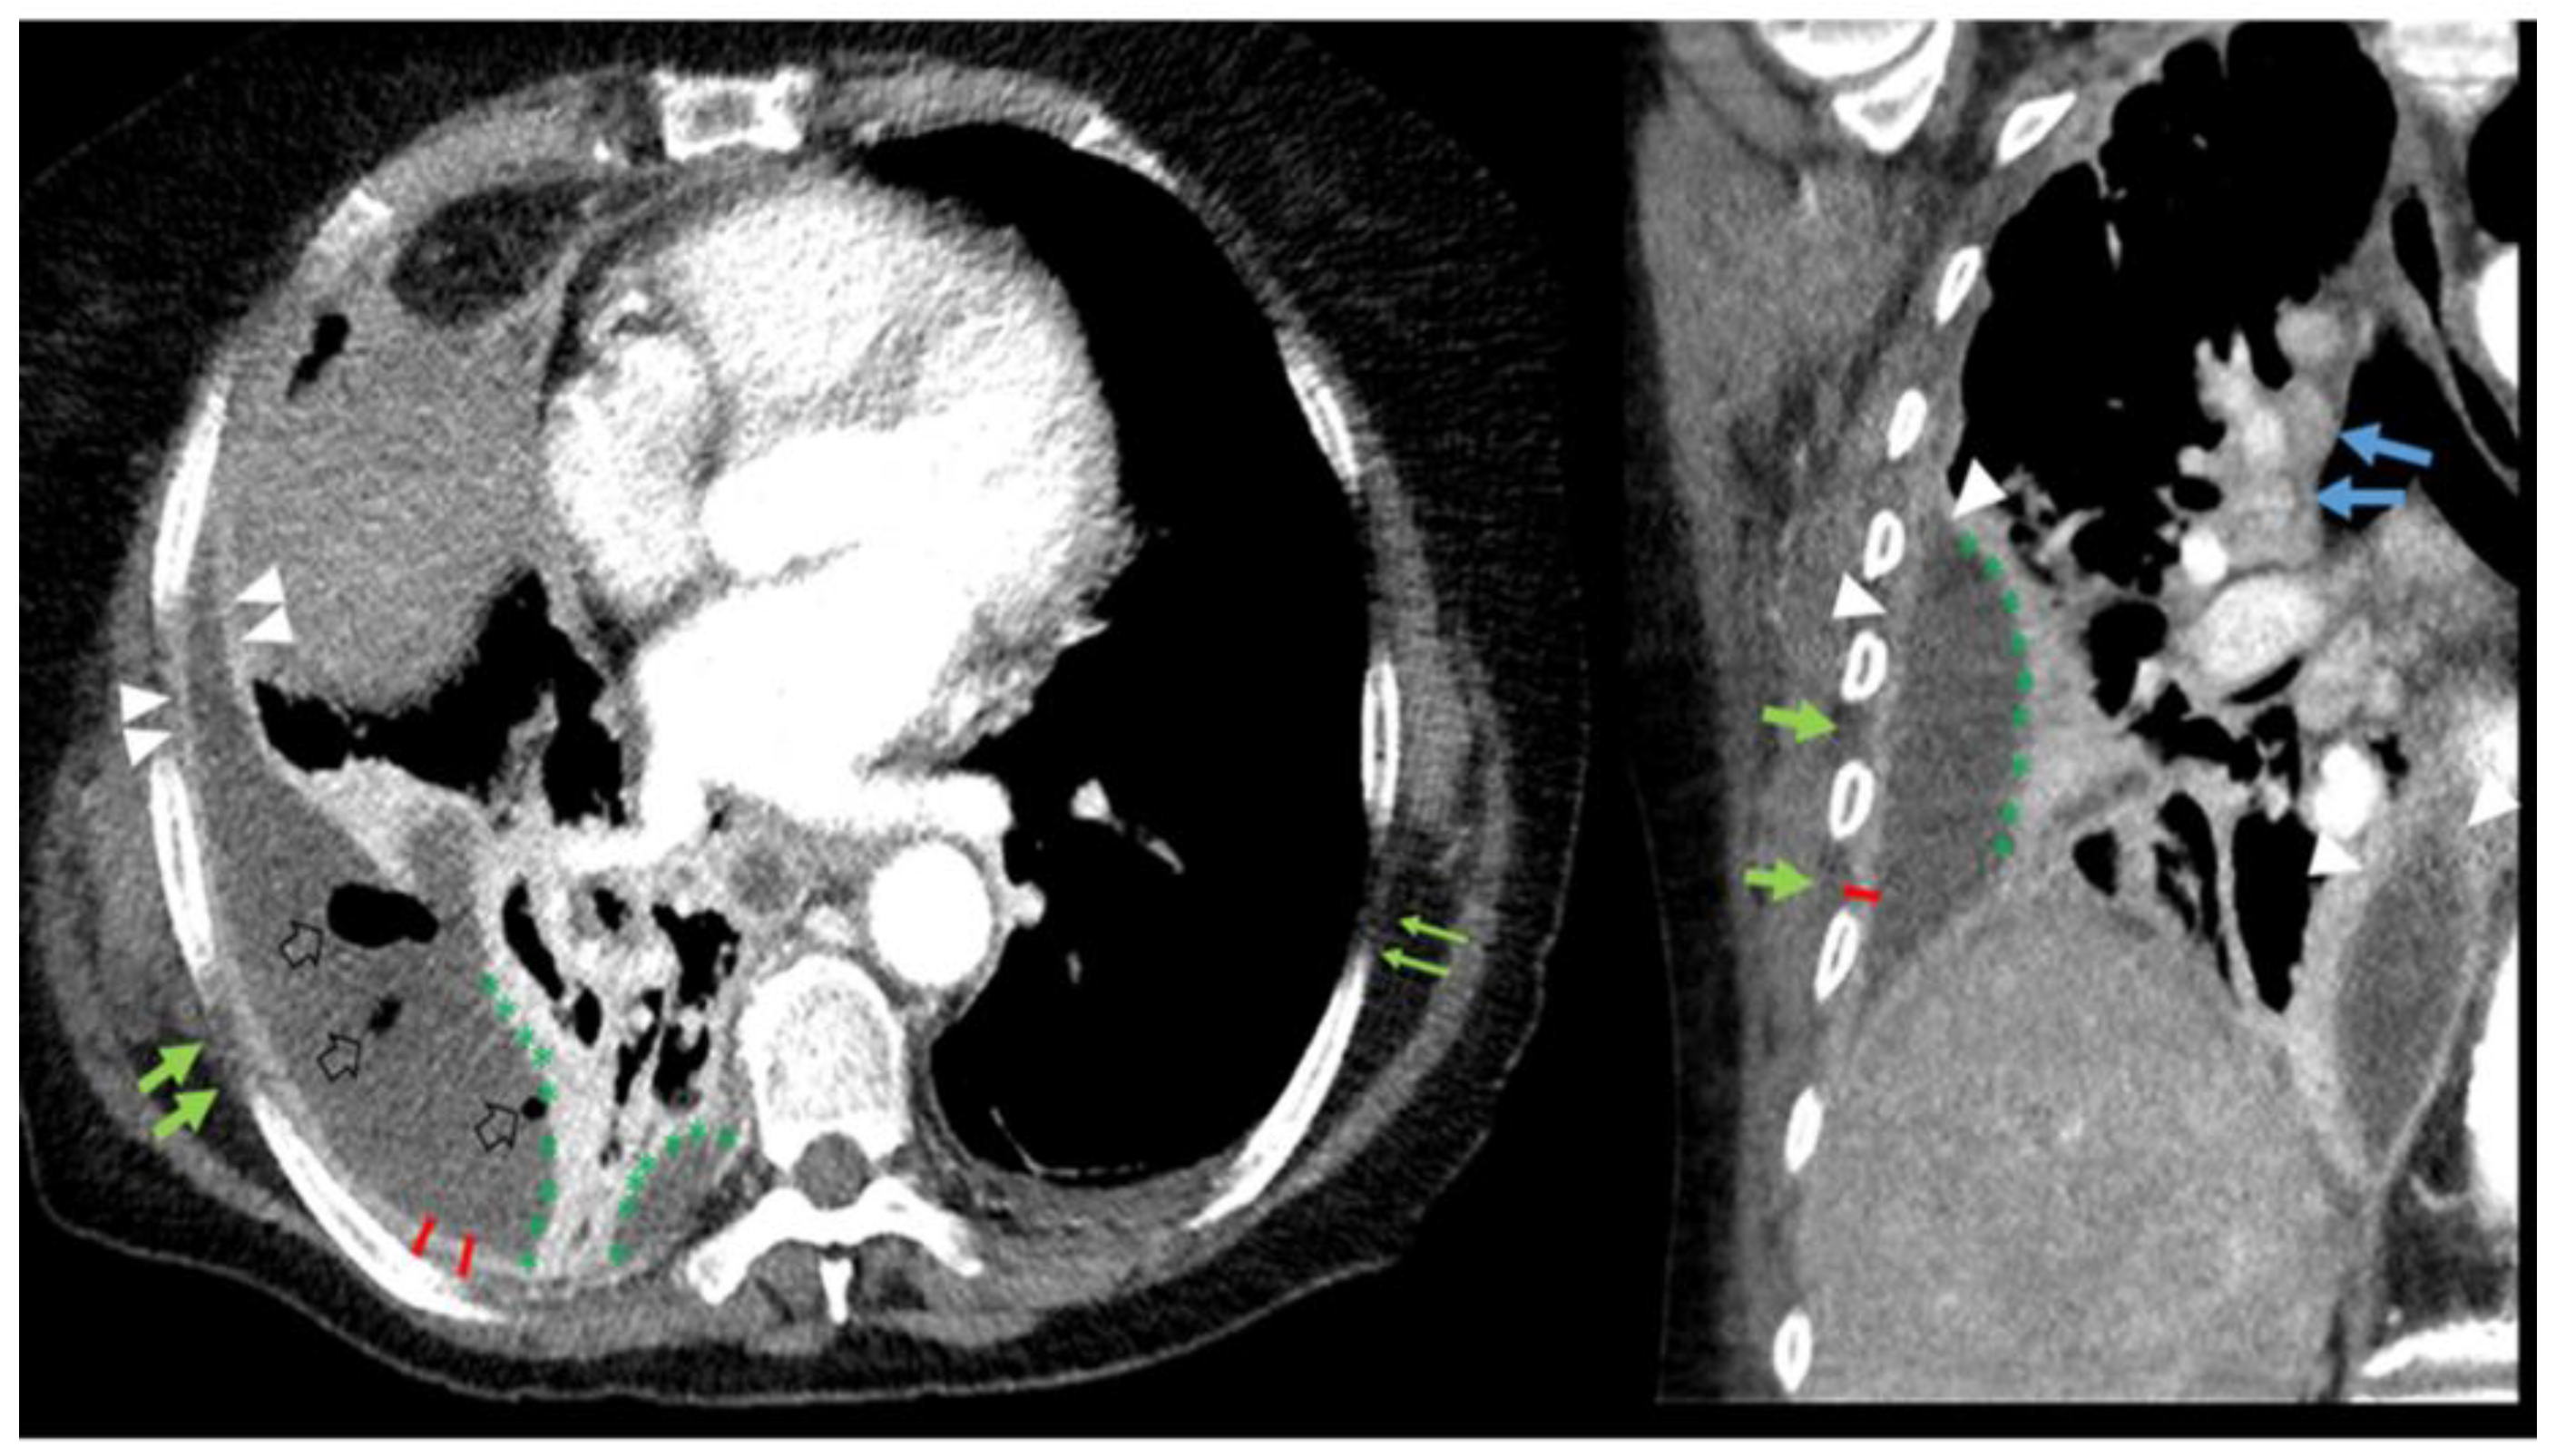

2.3. Pleural CT Features

2.3.2. Prespecified CT Based CT Feature Extraction